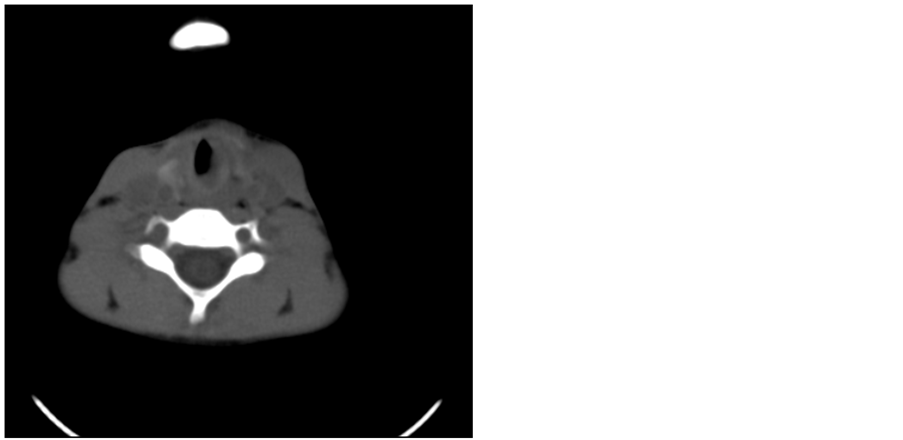

A 13 years old girl presented to our out patient department with the complaints of shortness of breath since 2 years. Shortness of breath started insidiously and gradually progressed to grade 3 [according to NYHA scale] dyspnoea and noisy breathing at rest. It was associated with hoarseness of voice and deterioration in voice quality. There was no history of hematemesis, hemoptysis or dysphagia. She was being treated as a case of bronchial asthma with bronchodilators. On examination there was biphasic stridor. Videolaryngoscopy (Figure 1) showed a smooth swelling over posterior 2/3rd of left vocal cord. Left vocal cord was not visible while right vocal cord was mobile and normal. Fibre-optic nasolaryngoscopy (Figure 2) was done which showed edema over left arytenoid and mass over left vocal cord and false cord. Right vocal cord was normal and mobile. Patient was advised a contrast enhanced CT scan (Figure 3).

Figure 3. CECT neck revealed a heterogenous edematous thickening of left vocal cord and aryepiglottic fold with narrowing of glottic airway measuring 8 × 7 mm suggestive of an inflammatory aetiology and less likely of a neoplastic process.